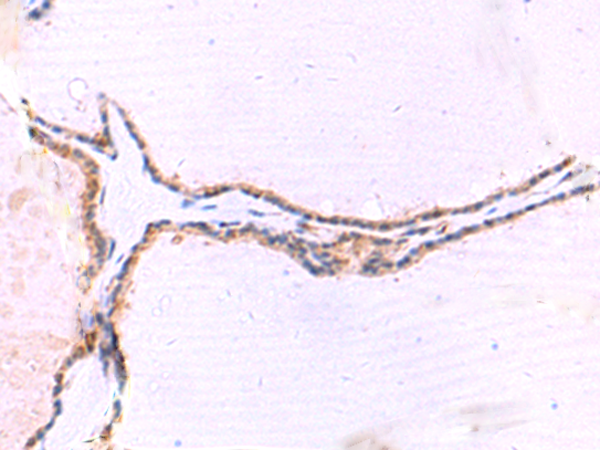

Applications:

ELISA, IHC

IHC positive control:

Human liver cancer and Human thyroid cancer

IHC Recommend dilution:

30-150